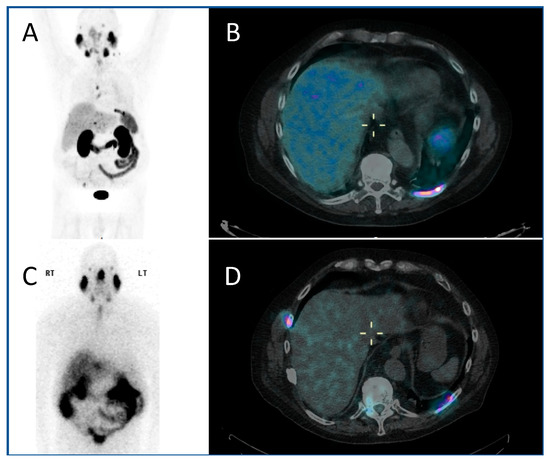

123I mIBG (meta-Iodobenzylguanidine) scintigraphy is the gold standard imaging modality for staging in neuroblastoma (Figure 1A,B), and various semi-quantitative systems have been devised which correlate with prognosis [15,16,17]. Over 90% of patients with neuroblastoma express the noradrenaline transporter molecule and so take up mIBG [18], and scintigraphic demonstration of this is used to select patients for 131I mIBG therapy (Figure 1C,D) [19].

Figure 1.

An example of a theragnostic pairing of radiopharmaceuticals in a child with metastatic neuroblastoma. Diagnostic 123I-mIBG imaging (A) anterior and (B) posterior views of whole-body planar scintigraphy demonstrating pathological uptake in a large left sided retroperitoneal mass as well as in metastatic disease in the femora and jaw, as well as physiological uptake in the salivary glands, heart, liver, urinary bladder and (despite blockade) in the thyroid gland. Corresponding (C) anterior and (D) posterior images following 131I-mIBG therapy administration showing uptake of the agent in the tumour and metastases as well as in physiological sites.